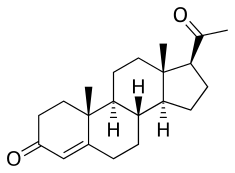

Chemistry

Progesterone is a naturally occurring pregnane steroid and is also known as pregn-4-ene-3,20-dione.[159][160] It has a double bond (4-ene) between the C4 and C5 positions and two ketone groups (3,20-dione), one at the C3 position and the other at the C20 position.[159][160]